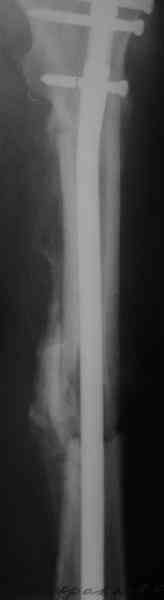

СМ> Если имеются под рукой Р-снимки, продемонстрируйте, плиз.

Вот несколько. С тисками и трубой на днях сделаем.